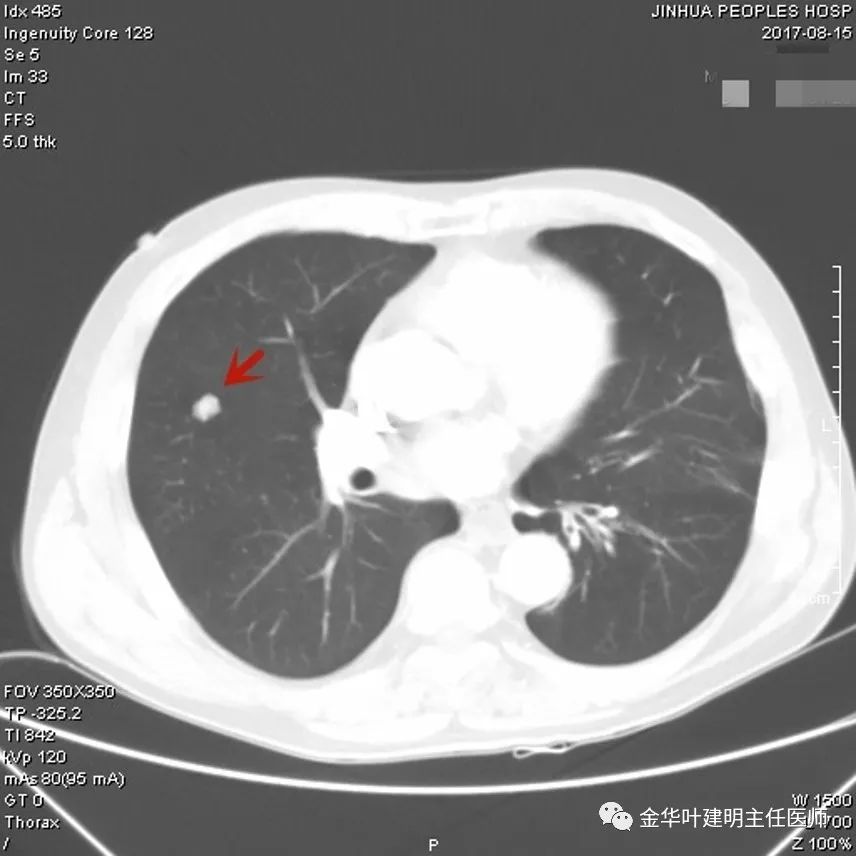

上图示浸润性腺癌典型表现。实性结节,有细毛刺征,有血管进入病灶,部分地方有浅分叶。